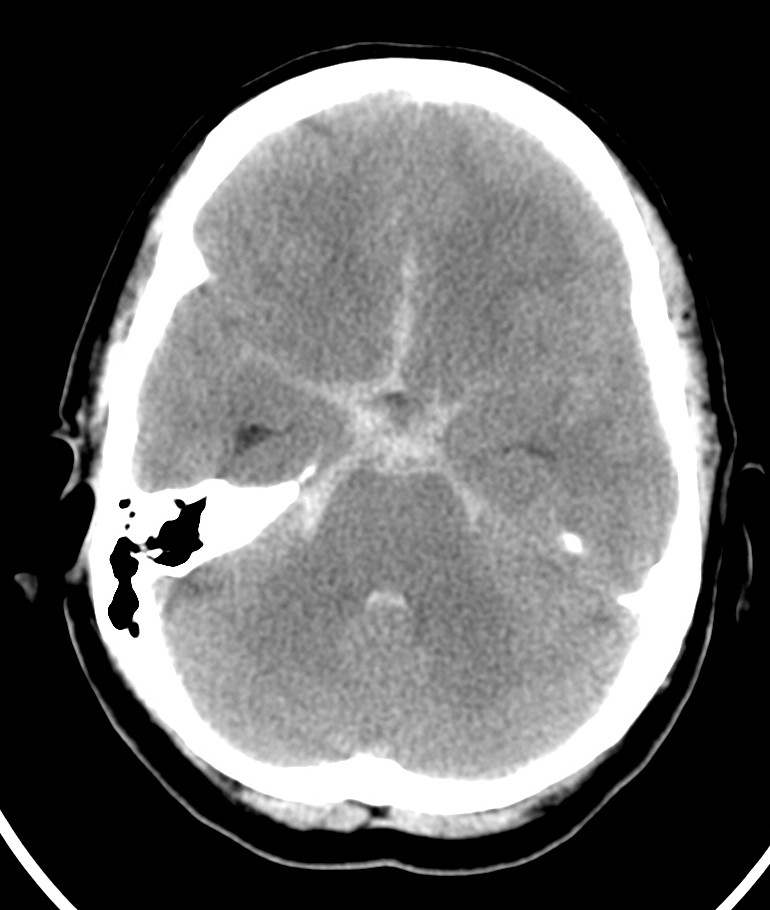

Se realiza TC de cráneo sin contraste, objetivándose:

Aunque la RM tiene mayor sensibilidad para el diagnóstico de sangrado, es la TC la prueba de primera línea debido a su mayor disponibilidad. Observaremos la característica imagen de hiperdensidad en las cisternas basales que corresponde a la sangre extravasada. La mayoría de las veces veremos el característico aumento de densidad alrededor del polígono de Willis (65%), que es donde ocurren la mayoría de las roturas de aneurismas, y también en la región de la cisura de Silvio (30%). Podemos ver también sangre en la fosa interpeduncular o asta occipital de los ventrículos laterales.

La TC ayuda a distinguir la ruptura aneursimática espontánea del sangrado tras traumatismo. Si la causa es un trauma, veremos el sangrado subaracnoideo confinado a los surcos superficiales de la convexidad del cerebro adyacente a la zona de fractura o contusión parenquimatosa. No obstante, si el traumatismo es en la región frontal, podemos ver sangre que simula una ruptura de aneurisma de la arteria cerebral anterior y cuando hay sangre en la cisura de Silvio o Ambiens, puede ser difícil distinguir entre traumatismo y aneurisma roto. Si el traumatismo es sobre el cuello, puede originarse un sangrado masivo que afecte las cisternas basares por afectación de las arterias de la circulación posterior.